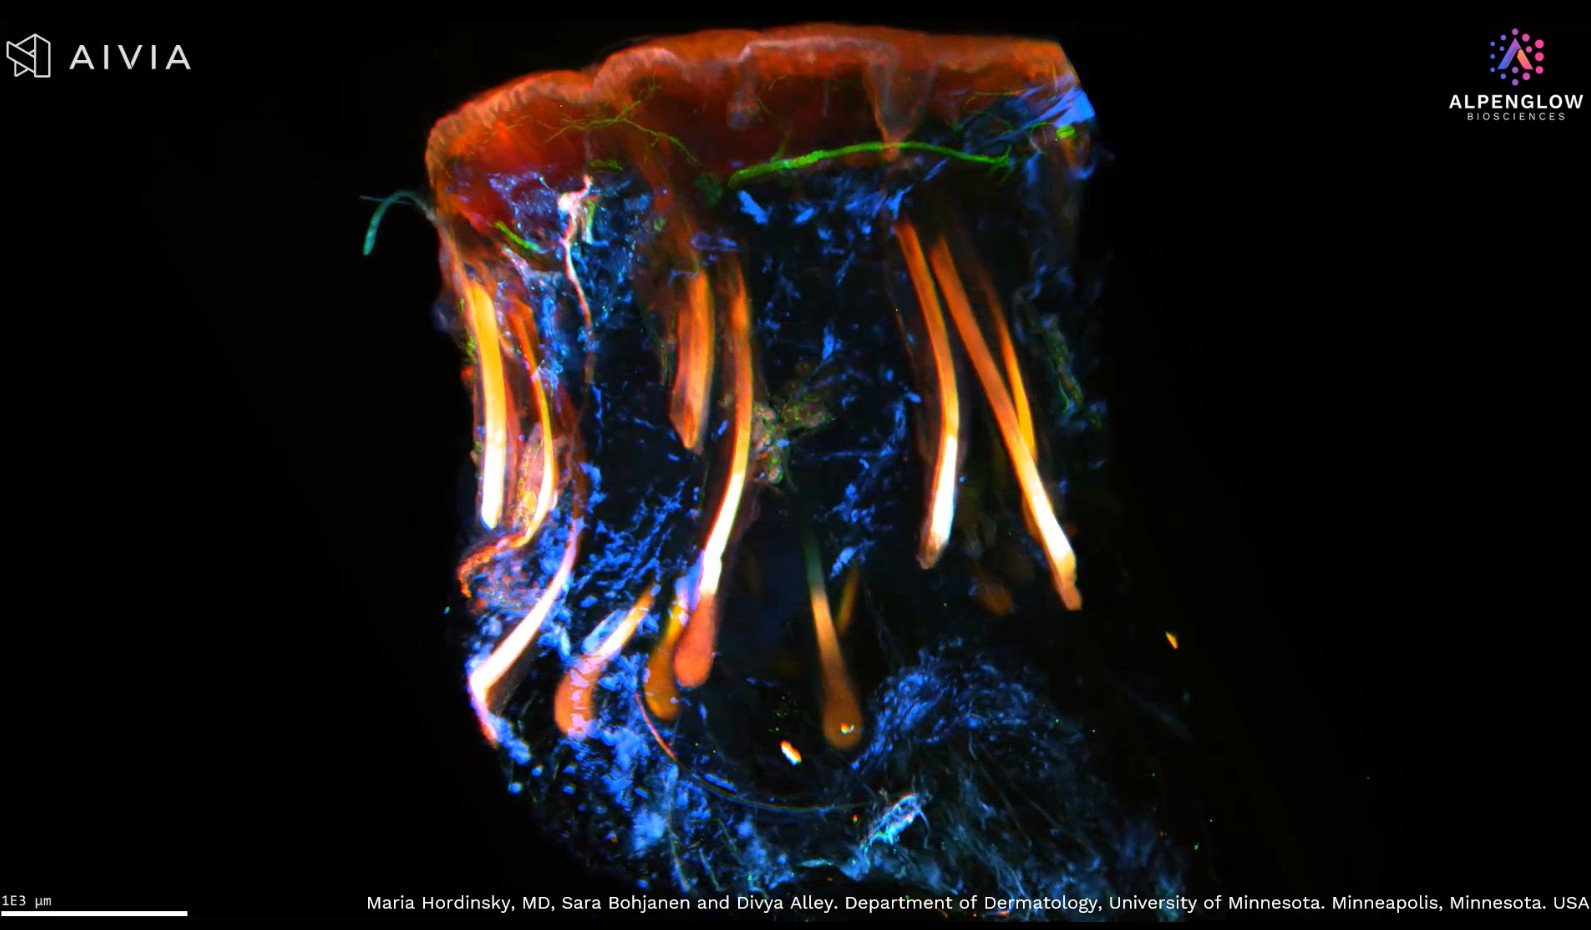

Unlocking the Secrets of Hair Follicles with 3D Imaging

See a hair follicle in stunning 3D detail, from the bulb to the dermal papilla. Using PGP9.5 and TO-PRO-3 staining, this advanced imaging highlights sensory nerve fibers and nuclei, transforming hair research and alopecia areata detection.